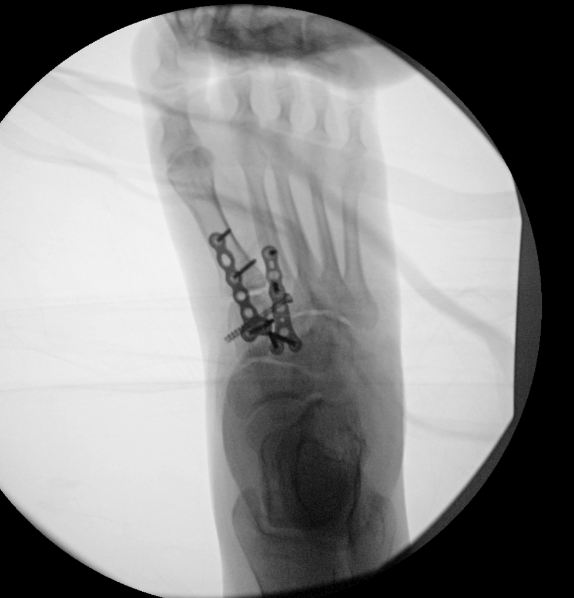

Surgical treatment of a Lisfranc injury addresses instability or fracture-dislocation of the midfoot joints that connect the forefoot to the midfoot. These injuries can lead to chronic pain and collapse if not treated appropriately.

Lisfranc surgery involves realigning the affected joints and stabilizing them using screws or plates. In some cases, primary fusion of the injured joints may be recommended to improve long-term outcomes.